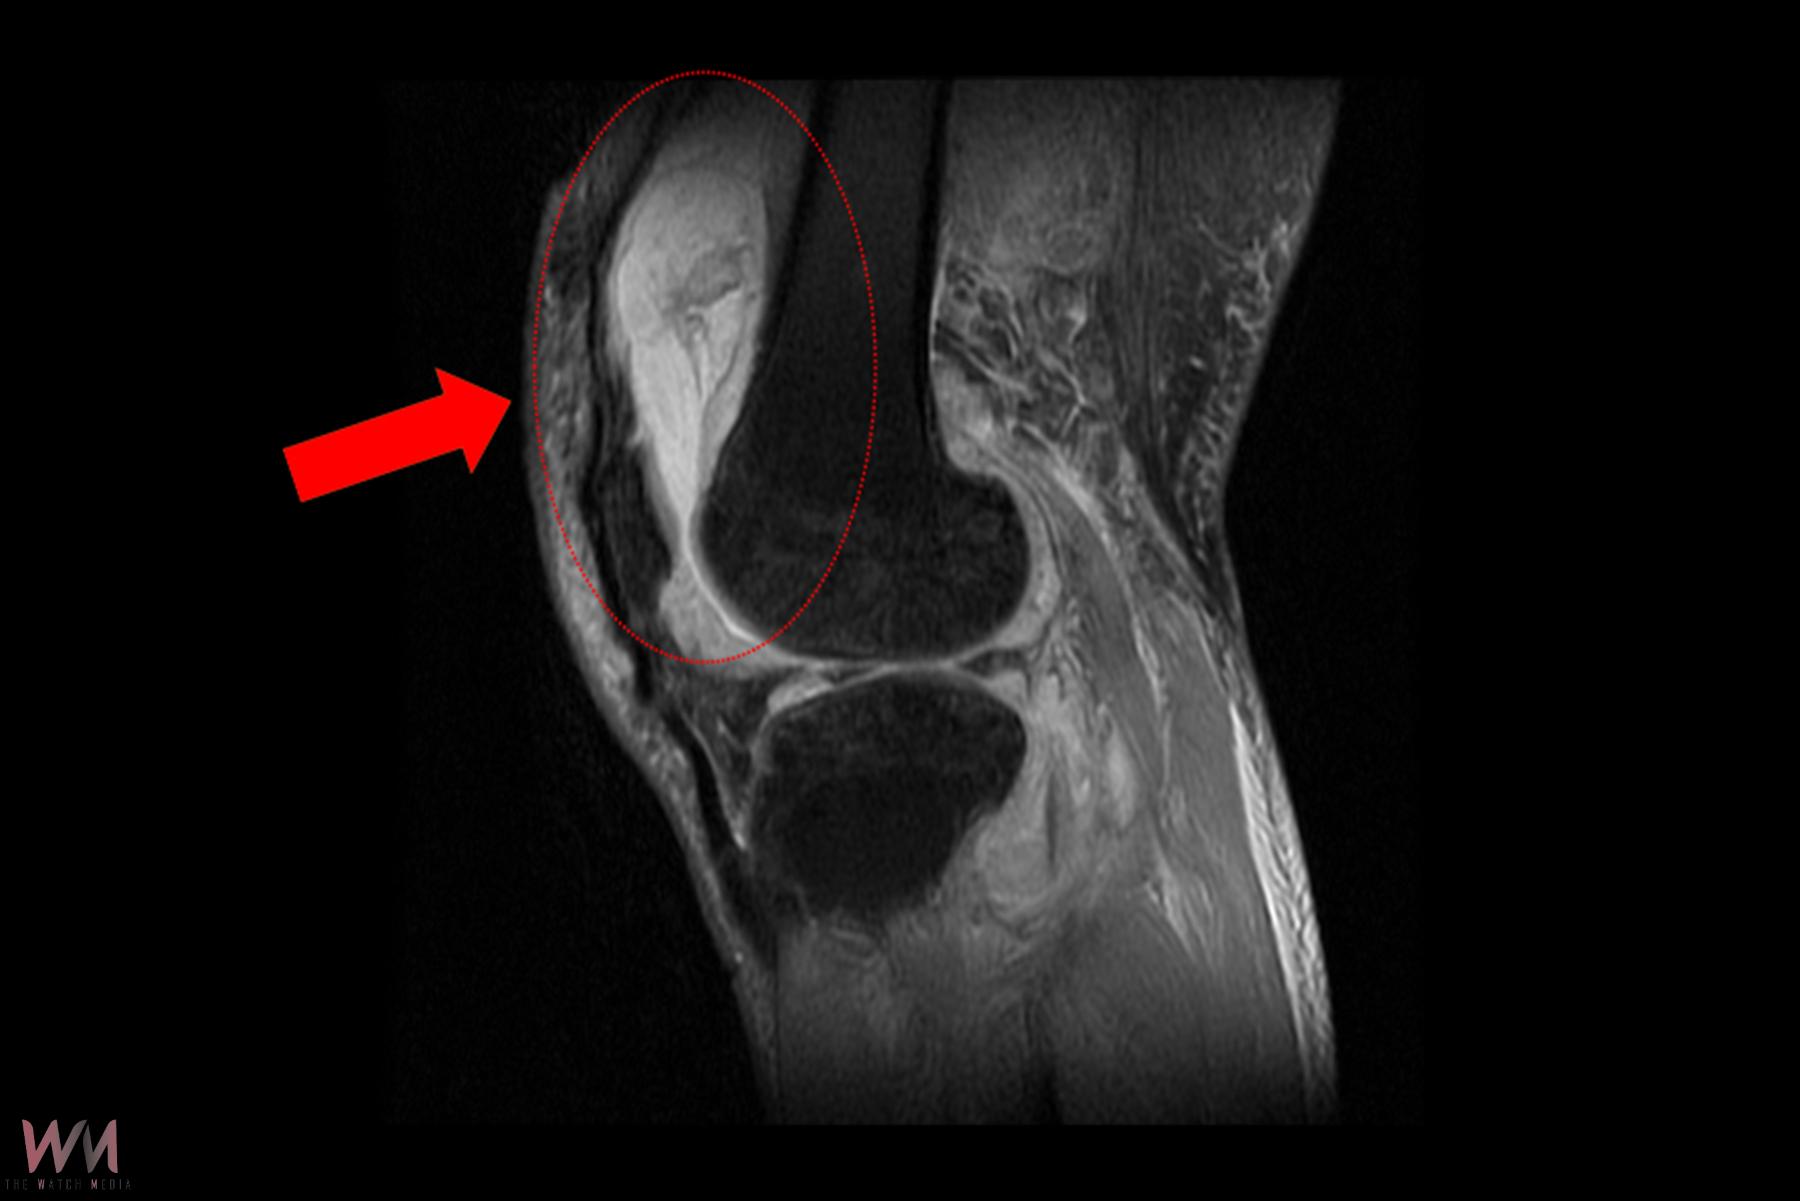

賴先生長期左膝腫痛、幾乎無法行走,就診時表示以為只是退化性關節炎,服用止痛藥、抽關節積水、熱敷復健數月卻越來越嚴重,來院時膝蓋已腫脹無法彎曲。關節中心主任周立展抽取膝關節液化驗後發現,白血球數值雖偏高,但並非典型的細菌感染,懷疑有其他原因。周主任安排病人住院,進一步X光與磁振造影檢查,顯示膝蓋內已有大量積液並化膿,屬於嚴重關節感染。

周立展主任避免病人感染惡化,緊急施行微創關節鏡清創手術,檢體送病理化驗後竟發現結核分枝桿菌,顯示並非單純膝蓋退化。周主任會診感染科與胸腔科醫師共同診斷,在病人痰液培養出結核菌,證實為「肺結核合併肺外感染」。結核菌最初在肺部引起感染,再經由血液或淋巴傳播,最後侵犯膝關節。病人住院期間接受抗結核藥物治療,一周後膝蓋腫脹消退,可正常彎曲行走;出院後仍須持續服藥至少九個月,並定期門診追蹤,確保結核菌完全清除。

周立展指出,結核菌感染膝關節案例較為少見,因結核菌多半侵犯肺部,侵犯膝關節或脊椎的比例不到一成。賴先生沒有慢性咳嗽、胸悶、發燒等典型的肺結核相關症狀,初期難以診斷。除了膝關節,脊椎或其他關節如肩、腕關節也都可能被結核菌侵犯。若賴先生延誤治療,結核菌會逐漸侵蝕關節骨頭,最嚴重就可能必須置換人工膝關節。